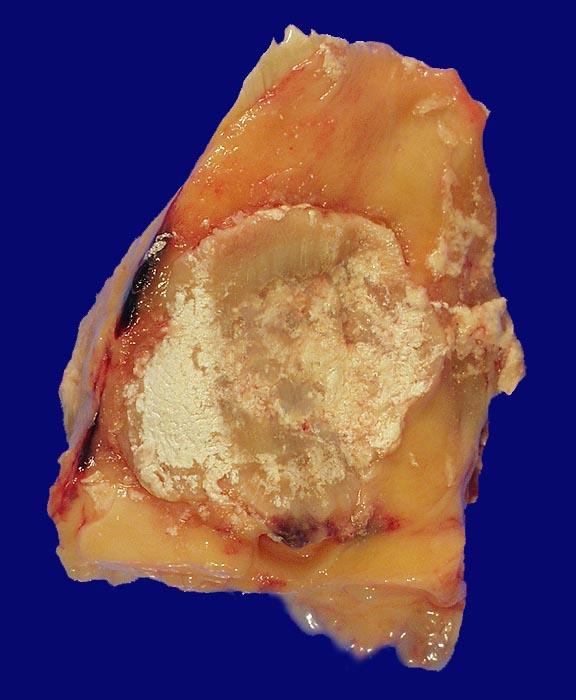

PathoPic ID 78 - Arthritis urica

Arthritis urica

Weisse Ablagerungen (Uratkristalle) auf der Hinterseite der Patella bei Arthritis urica